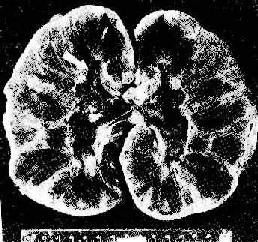

图4-6 肾移植急性排斥反应

肿胀,明显出血,肾盏及肾盂中充满血块